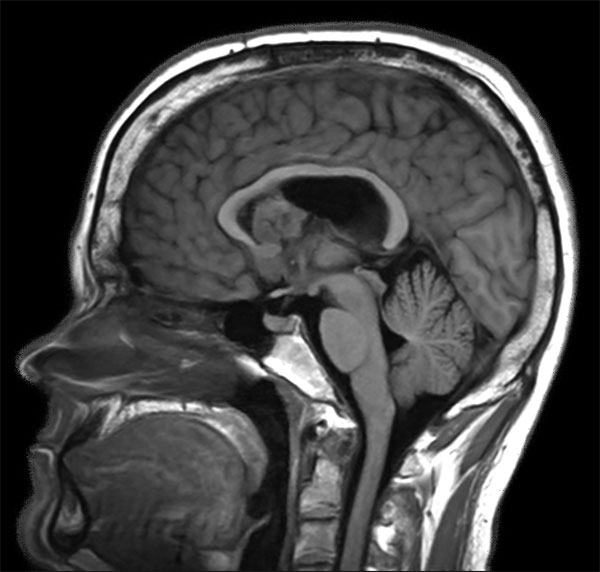

Sagittal T1W IR TSE